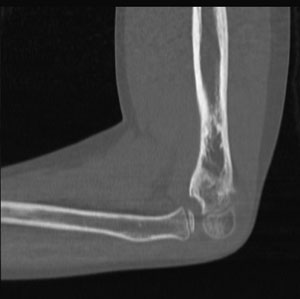

X-rays are a form of “ionizing radiation” which has enough energy to penetrate the body, which enables X-rays to produce pictures or images of internal body structures. X-rays are also used to assist with interventional procedures and to target and destroy abnormal cells during radiation therapy.